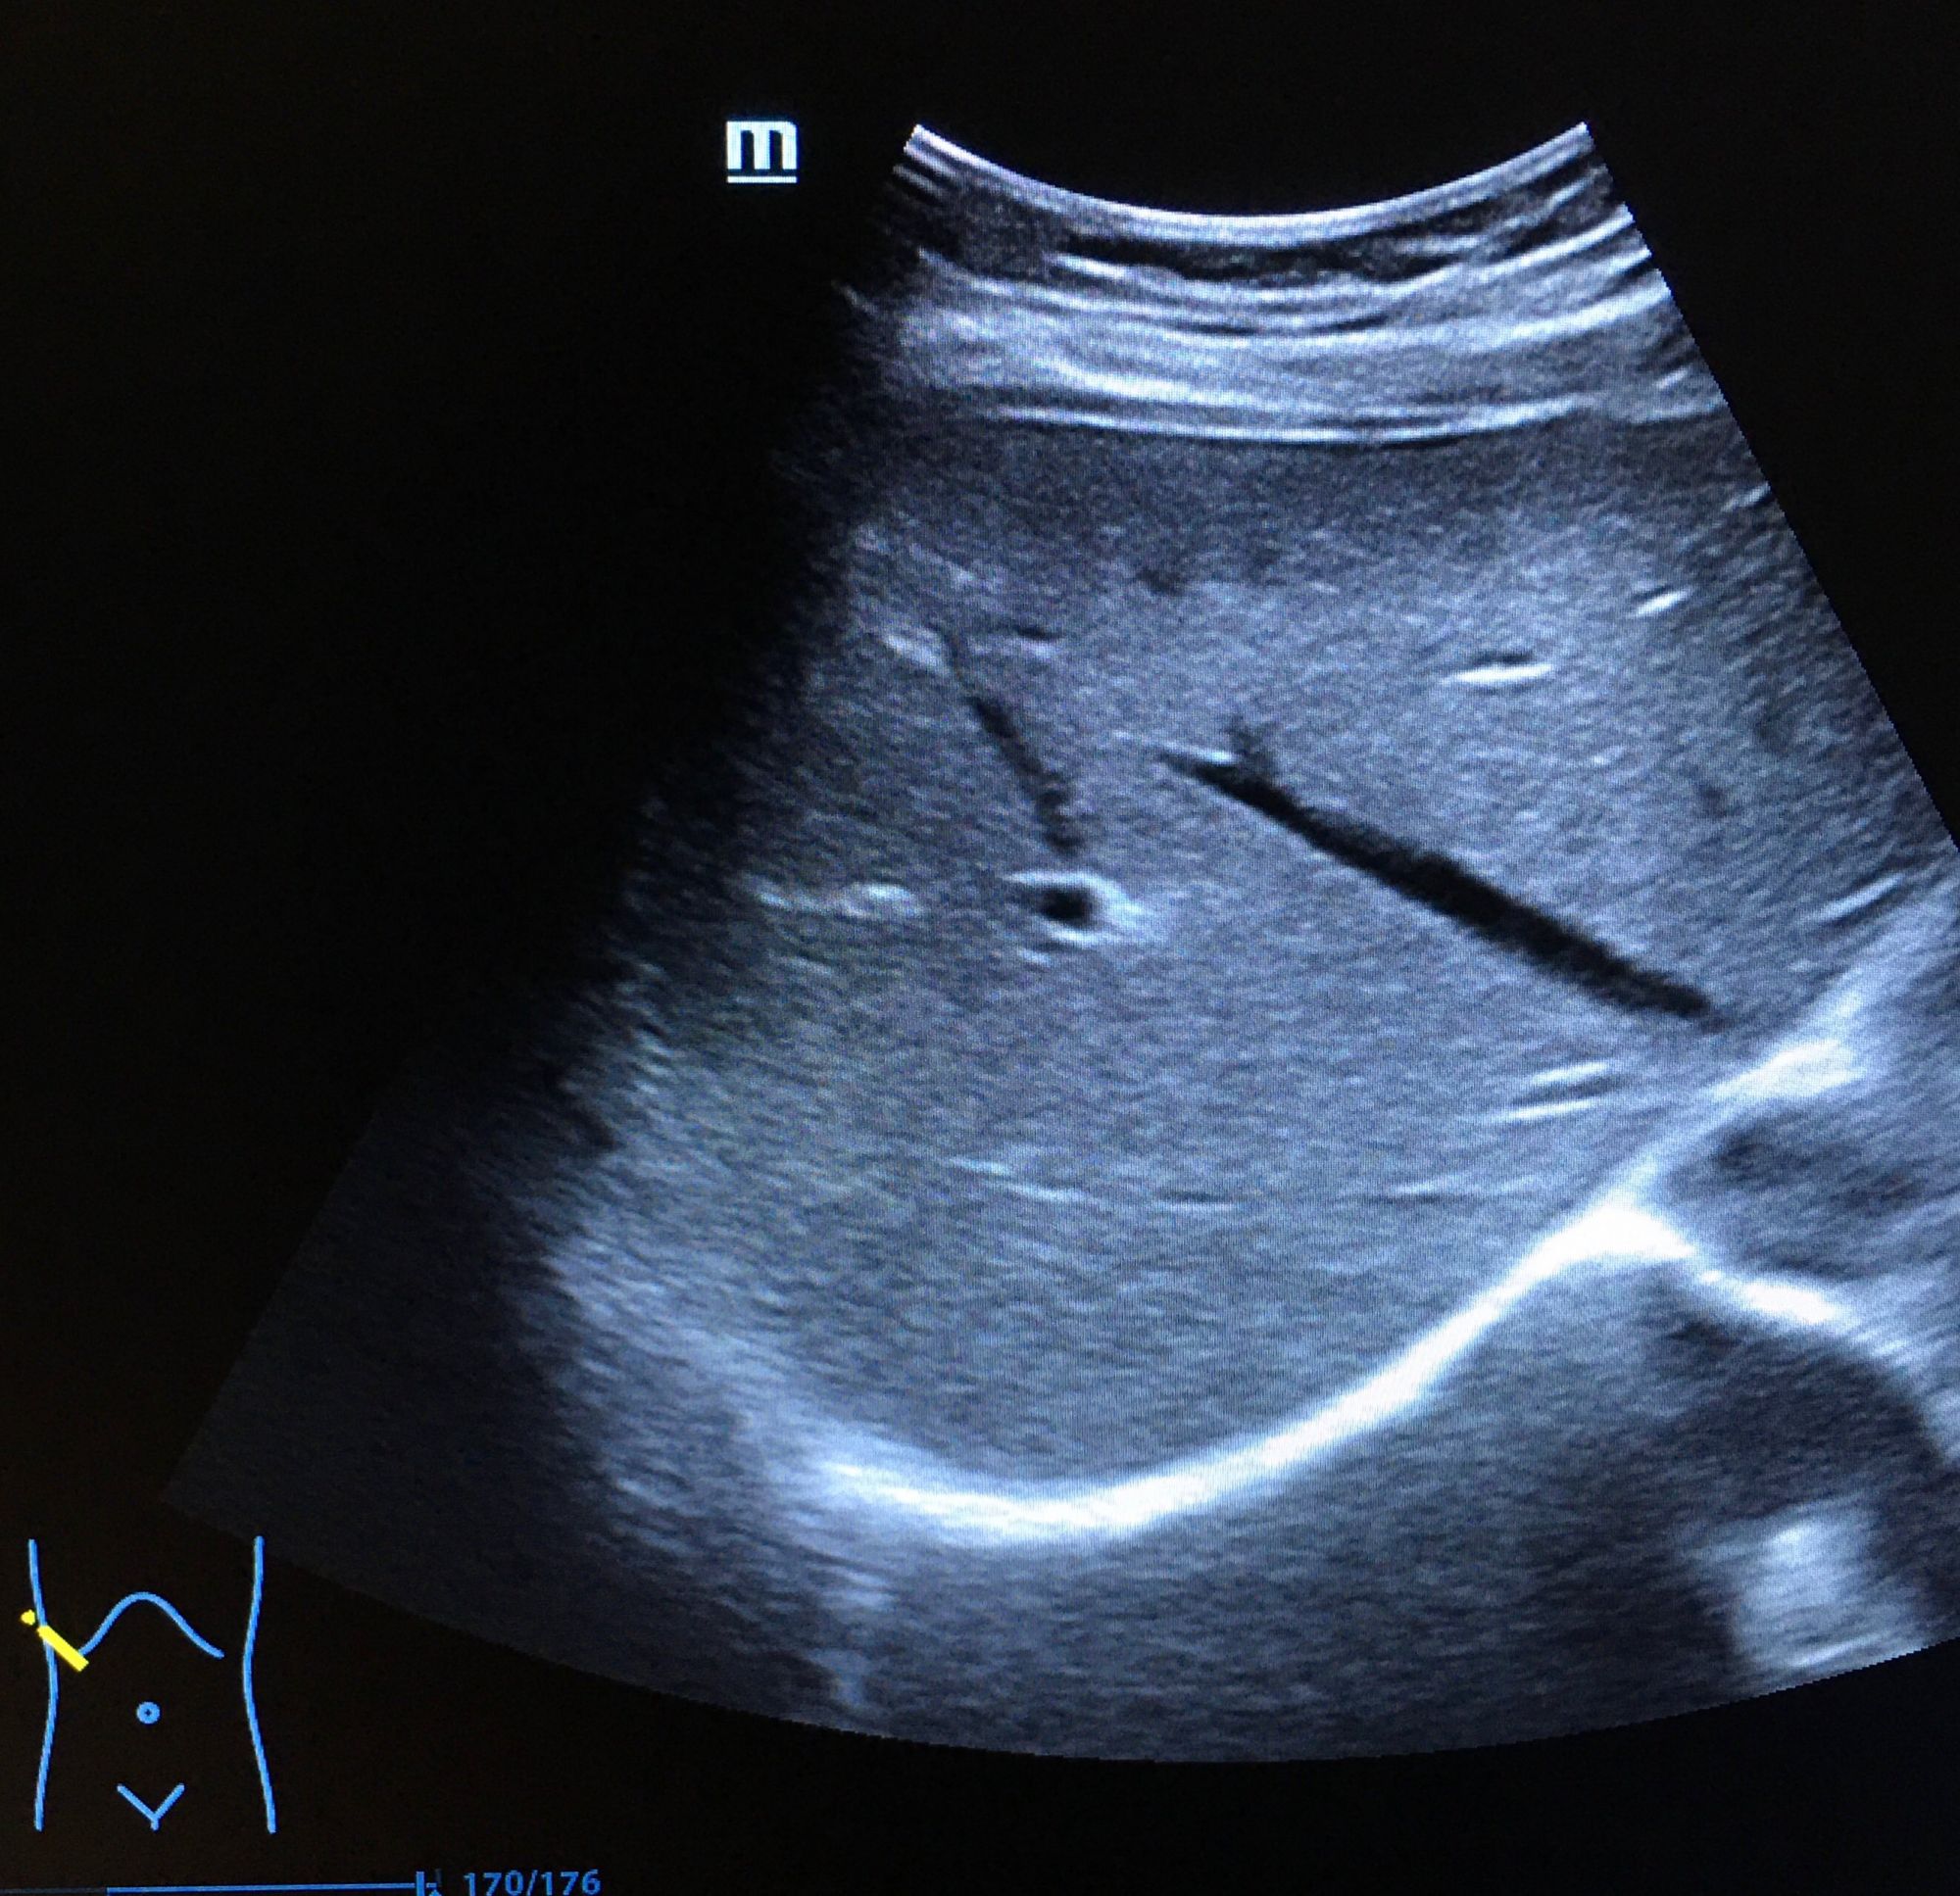

二、超聲成像

是一種基于超聲波的成像技術。超聲波在生物體內傳播時,遇到不同的組織會產生不同的回聲信號,通過分析這些信號可以獲取生物體的內部結構和功能信息。超聲成像具有無創(chuàng)、無痛、無輻射等優(yōu)點,因此在臨床診斷和生命科學研究中得到了廣泛應用。

超聲成像